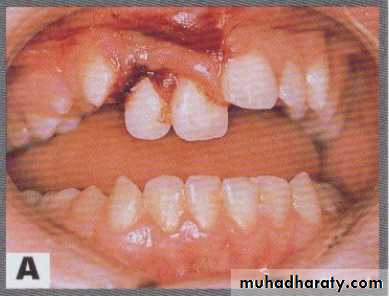

EXTRUSIVE LUXATION

Tooth displace axially from the socketDiagnosis; clinically appear longer and is mobile

On radiograph; PDL space is increased apically

treatment; reposition tooth with gentle and firm digital pressure

splint for 2wks

Follow-up; closed apex are at risk of necrosis hence, pulp therapy is indicated after splinting

Note teeth appearing longer